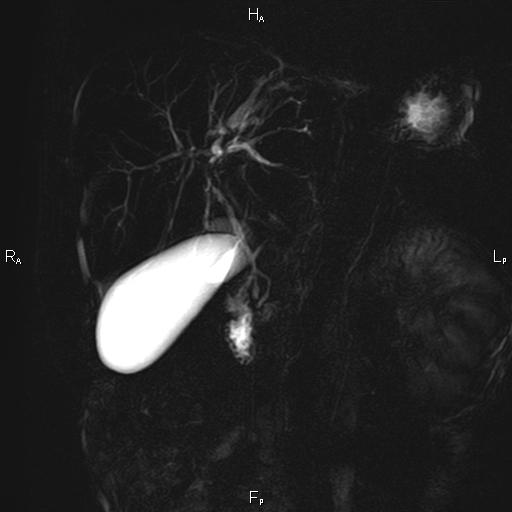

ΚΛΙΝΙΚΑ ΣΤΟΙΧΕΙΑ – ΙΣΤΟΡΙΚΟ

Ανώδυνος ίκτερος και παθολογικά ηπατικά ένζυμα. Ιστορικό πιθανής σκληρυντικής χολαγγειίτιδας

ΑΠΕΙΚΟΝΙΣΤΙΚΟΣ ΕΛΕΓΧΟΣ

Μαγνητική τομογραφία.

Οι αρχικές εξετάσεις εκλογής, όσον αφορά τον απεικονιστικό κυρίως έλεγχο, σε ασθενή προσερχόμενο στο Νοσοκομείο με αποφρακτικό ίκτερο, είναι το υπερηχογράφημα και η αξονική τομογραφία. Οι εξετάσεις αυτές έχουν αποδειχθεί ικανές να προσδώσουν έμμεσα και άμεσα στοιχεία για τη διάγνωση του χολαγγειοκαρκινώματος, όμως κυρίαρχη εξέταση για την διάγνωση του χολαγγειοκαρκινώματος είναι η μαγνητική τομογραφία (MRI, MRCP, MRA).